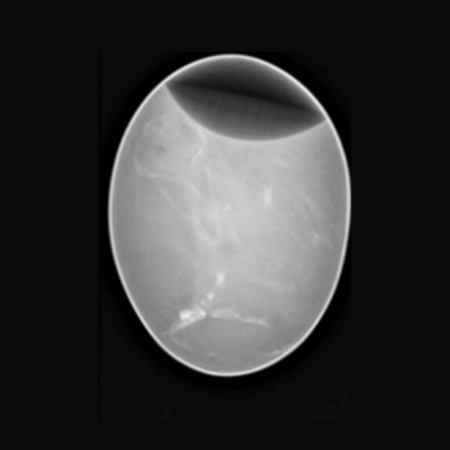

Chicken Egg

Chicken Egg. Image Credit: Scintica Instrumentation Inc